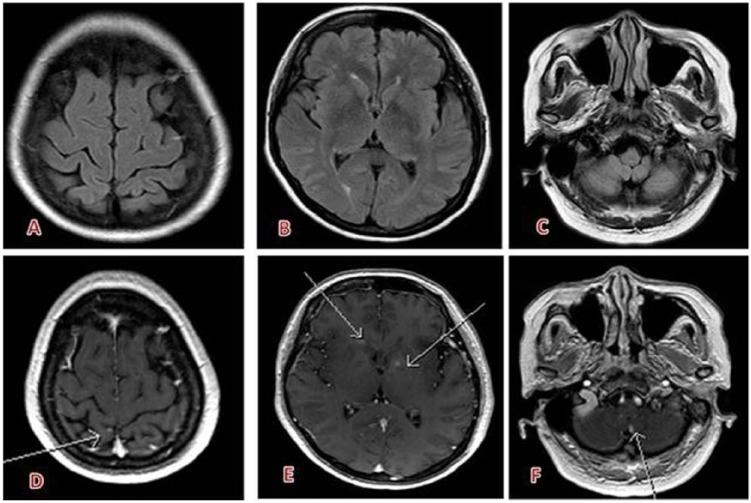

Gadobutrol is a gadolinium (Gd)-based contrast agent for magnetic resonance imaging (MRI). In India, gadobutrol is approved for MRI of the central nervous system (CNS), liver, kidneys, breast and for MR angiography for patients 2 years and older. The standard dose for all age groups is 0.1 mmol/kg body weight. The safety profile has been demonstrated in 42 clinical phase 2 to 4 studies (>6800 patients), 7 observational studies, and by assessing pharmacovigilance data of 29 million applications. Furthermore, studies in children, adults, and elderly and in patients with impaired liver or kidney function did not show any increased adverse event rate. Diagnostic efficacy was demonstrated in numerous studies and various indications, such as diseases of the CNS, peripheral and supra-aortic vessels, kidneys, liver, and breast.

钆布醇是一种用于磁共振成像(MRI)的基于钆(Gd)的造影剂。在印度,钆布醇被批准用于2岁及以上患者的中枢神经系统(CNS)、肝脏、肾脏、乳腺的MRI检查以及磁共振血管造影。所有年龄组的标准剂量为0.1 mmol/kg体重。在42项2期至4期临床研究(>6800例患者)、7项观察性研究以及通过评估2900万份用药的药物警戒数据中均已证明了其安全性。此外,在儿童成人、老年人以及肝肾功能受损患者中进行的研究并未显示不良事件发生率有任何增加。在众多研究以及各种适应症(如中枢神经系统疾病、外周和主动脉上血管疾病、肾脏疾病、肝脏疾病和乳腺疾病)中均证实了其诊断效能。